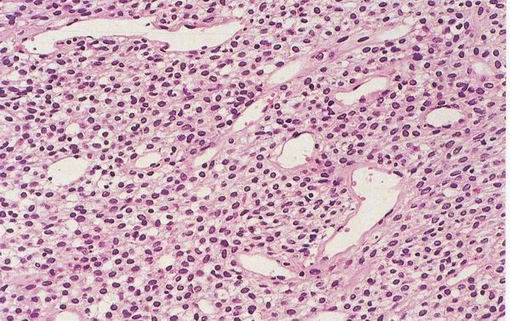

Sinonasální haemangiopericytom

Sinonasální haemangiopericytom (CAVE! odlišný od konvenčního haemangiopericytomu - nejsou nekrózy, atypie, atypické mitózy ani vysoká mitotická aktivita)